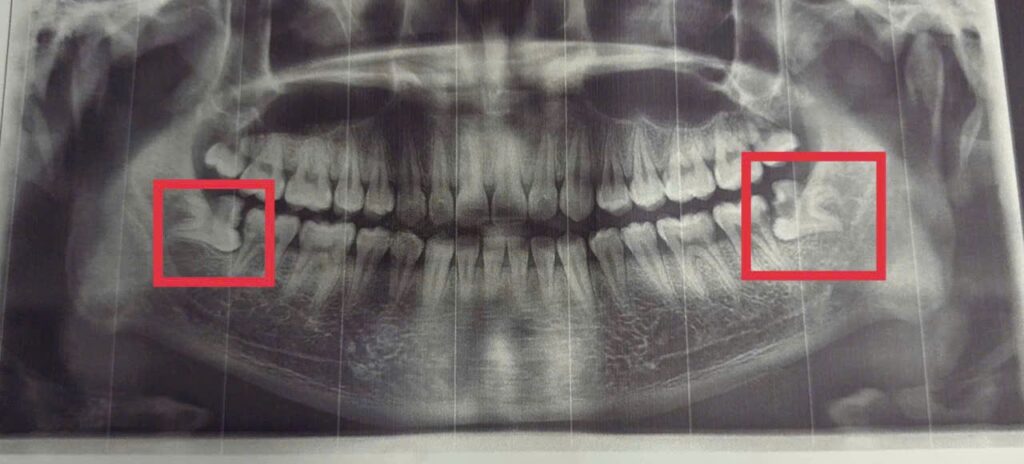

- Thăm khám và chẩn đoán hình ảnh, xét nghiệm cận lâm sàng kỹ lưỡng: Chụp phim X-quang như: phim Panorex hoặc CT Conebeam để bác sĩ đánh giá chính xác vị trí, hướng mọc của răng, mức độ phức tạp và mối liên quan đến dây thần kinh, xoang hàm; làm xét nghiệm cơ bản như công thức máu và chức năng đông máu đảm bảo ca tiểu phẫu cầm máu an toàn.